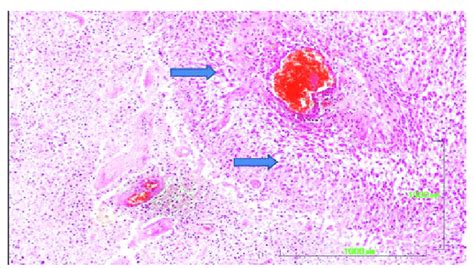

Let’s zoom in, guys, and talk about what pseudopalisading actually looks like under the microscope. It’s all about the arrangement of cell nuclei, which are the control centers of the cells. Imagine you have a patch of dead or dying tissue right in the middle of your sample – that’s the area of necrosis. Now, surrounding this necrotic core, you’ll see a layer of living cells. In pseudopalisading, these living cells, or more specifically, their nuclei, form a somewhat linear, row-like pattern. But here’s the kicker: it’s not a perfectly straight, neat row like a picket fence. Instead, the nuclei are often elongated and crowded together, appearing aligned on one side of the necrotic area. They might look like they’re pushing towards the dead tissue, trying to get closer to it for some reason, or perhaps trying to wall it off. The key feature that differentiates it from true palisading (which is less common and often seen in benign conditions like schwannomas) is the irregularity and the presence of intervening cells or blood vessels . In true palisading, the cells are more uniformly spaced and orderly. In pseudopalisading, you might see gaps, overlapping cells, or a more haphazard arrangement. The nuclei themselves might also appear pleomorphic, meaning they vary in size and shape, which is often a sign of malignancy. Some might be dark and smudged, while others are larger and more irregularly shaped. The cells are often described as ‘spindled’ or ‘elongated’ as they orient themselves. Pathologists use special stains and high-powered microscopes to meticulously examine these patterns. They’re looking for this specific arrangement around foci of necrosis . It’s not just a few cells in a line; it’s a more extensive pattern. The presence of microvascular proliferation (new, small blood vessels forming) is often seen alongside pseudopalisading in aggressive tumors like GBM. This intricate dance of cells – the dying tissue, the reactive surrounding cells forming a messy line, and the often-associated abnormal blood vessels – creates a distinct microscopic picture. It’s this complex visual signature that provides invaluable diagnostic information, guiding the pathologist in making a crucial determination about the nature of the tissue.